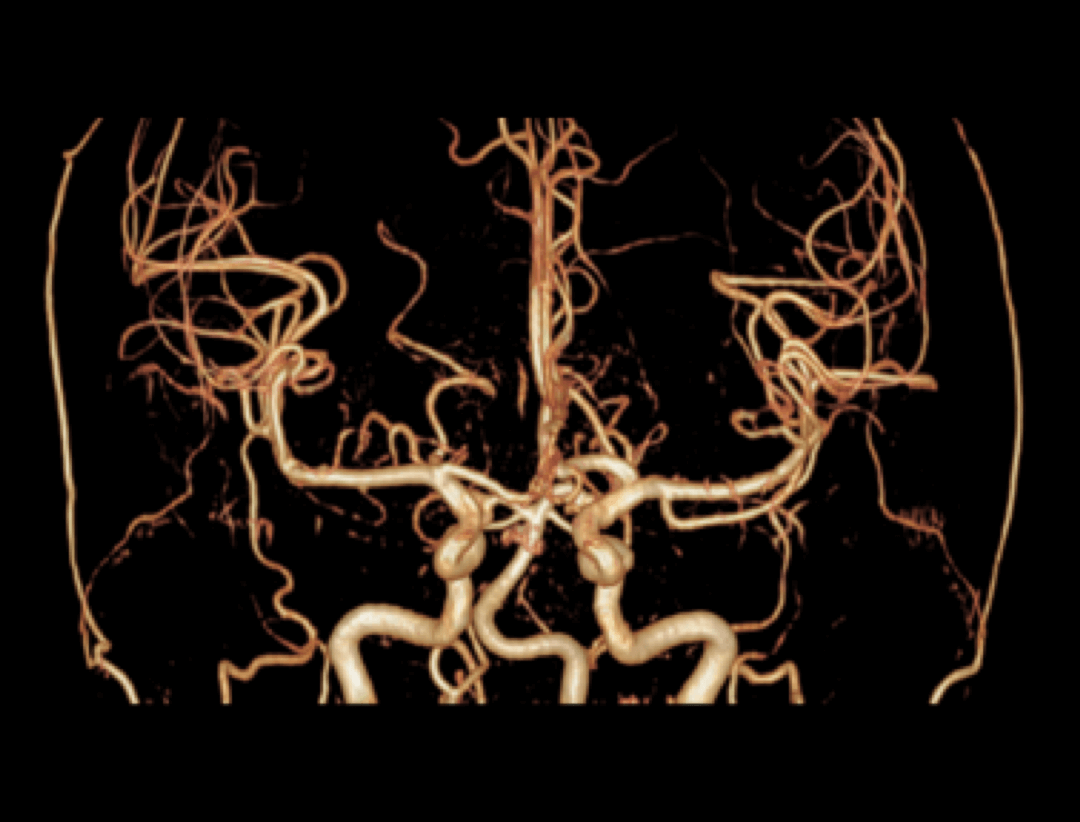

Galerie clinică

Neuro

NCE-MRA